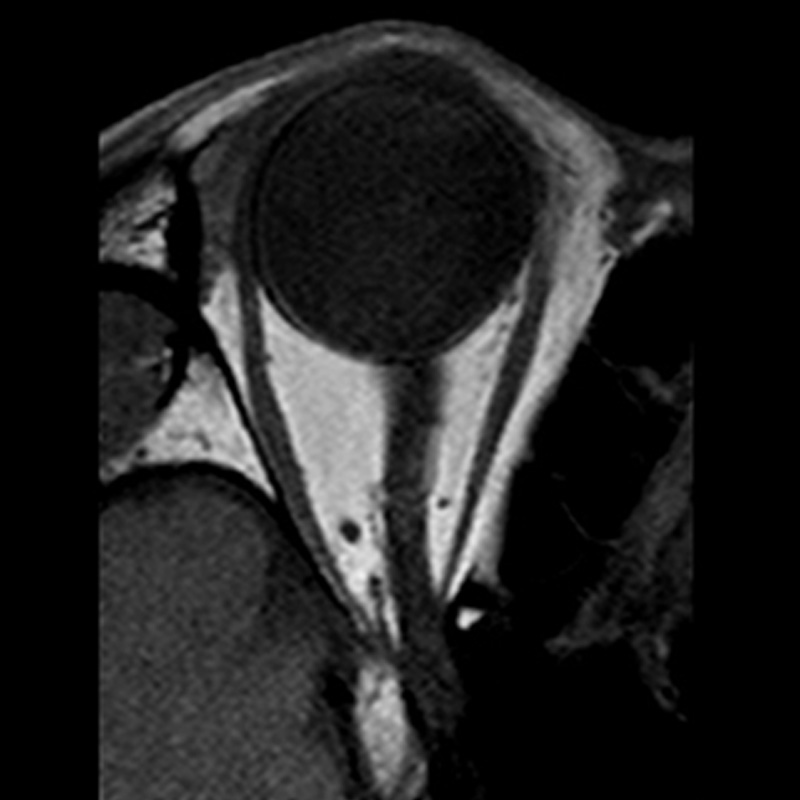

Axi T2w for orbit

Orbit image. Did not require a dedicated coil such as a circle coil to image the orbit. The image can be acquired in only 30 seconds using a normal head/neck coil with a small field of view (FOV) and low resolution. The structures around the lens are clearly visible.

Acquisition time: 0:36